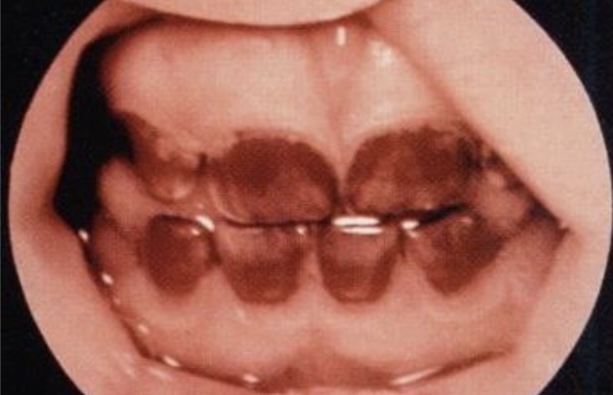

Wet gangrene

Dry gangrene